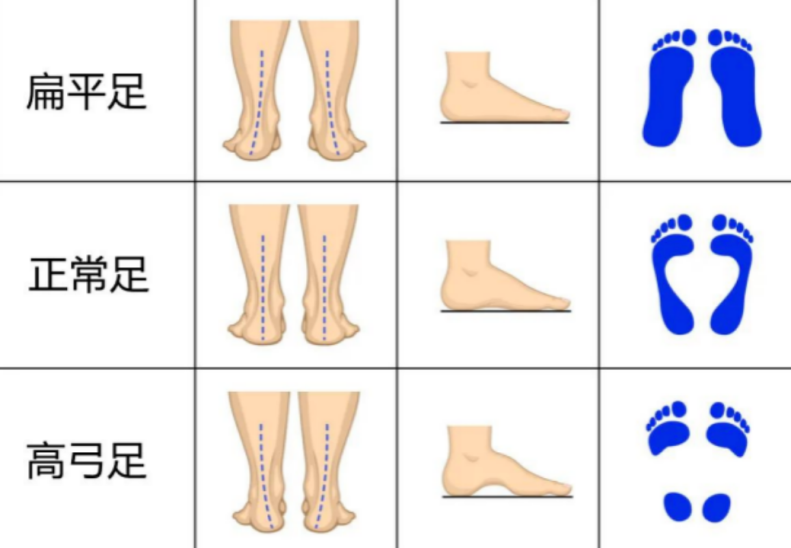

正常脚底内侧有一个拱形,从脚跟一直延伸到大脚趾的底部,我们称之为足弓。当脚没有足弓时,称为扁平足或平足。扁平足是常见的青少年临床问题之一,主要表现为足跟外翻,足内侧弓塌陷,前足外展,整个脚底负重,该病症患者负重力线不正常,发展到一定程度可出现足部疲劳或疼痛症状,从而出现不能长时间的站立和行走、奔跑和运动表现差的情况。